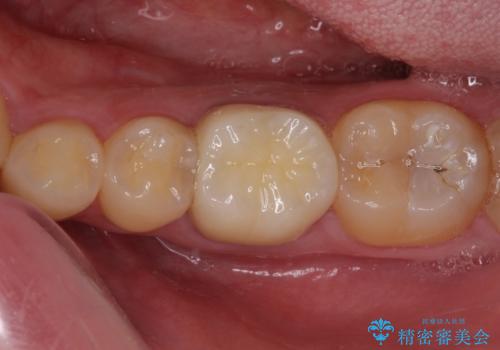

途中来院されない時期があったため、初診から終了まで期間がかかりましたが、根管治療を行った歯の根尖病変はいずれも改善を確認することができました。

口腔内の金属が全てなくなり、患者様には大変満足していただきました。